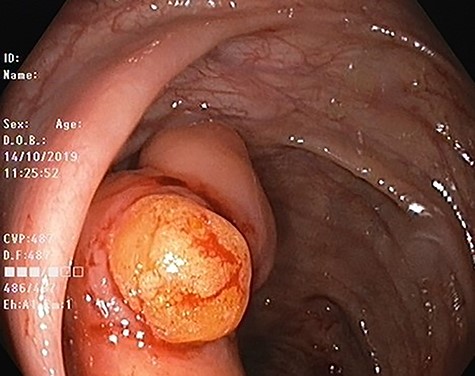

Our patient is 56-year-old female, a known case of locally advanced breast carcinoma. She was initially managed by chemotherapy followed by modified radical mastectomy then adjuvant radiotherapy and chemotherapy. The patient gave a positive family history of colon cancer; therefore, genetic testing for adenomatous polyposis coli (APC) mutation and surveillance colonoscopy were recommended by genetic counselor. The APC gene mutation came to be positive and as part of the work up for her primary disease, computed tomography (CT) scan of the abdomen performed and showed evidence of 4 cm intraluminal lesion in the ascending colon suggestive of lipoma without bowel obstruction (Fig. 1). As a result of these findings, colonoscopy was performed and it revealed a large smooth intraluminal subepithelial lesion in the ascending colon occupying one third of the lumen circumference (Fig. 2). With the use of biopsy forceps, indentation of the tumor can be seen, which is as known as “pillow sign” and once a biopsy taken, a fatty yellowish material was seen protruding from the biopsy site suggestive of lipoma (Fig. 3). Histopathological examination showed multiple fragment of normal colonic mucosa and fragments of mature adipose tissue consistent with lipoma (Fig. 4, black arrows). Clinically, the patient denied history of abdominal pain, rectal bleeding, changes in her bowel habit and intestinal obstruction symptoms. She denied any personal history of malignancy or lipoma. On physical examination, there was no evidence of any lipomas in particular her scalp, limbs or trunk. Although she has no gastrointestinal symptoms attributed to the lipoma, given that it is large in size and she is in clinical and radiological remission, we referred her for the opinion of colorectal surgery.

Colonoscopic image of ascending colon lipoma showing normal mucosa.

Colonic lipoma after biopsy showing typical yellowish adispose tissue.

Endoscopically, colonic lipoma is recognized easily as a well-delineated, soft, round or ovoid, yellowish sessile or pedunculated mass. Although the mucosa overlying the lipoma is usually intact, however, in rare cases ulcerations and erythema can be seen on the mucosa, which may lead to impression of malignancy. Because of the lipomas’ location in the submucosa, three endoscopic signs may contribute to the diagnosis: the ‘cushion sign’ (probing the polyp with a closed biopsy forceps will often yield a pillow-like indentation), the ‘tenting effect’ (grasping the overlying mucosa with biopsy forceps presents a tent-like appearance), and the ‘naked fat sign’ (biopsies may result in an extrusion of yellowish fat) [4]. Endoscopic ultrasonography (EUS) can be used to distinguish lipoma from other submucosal lesions such as leiomyoma and schwannoma. On EUS, lipoma appears as hyperechoic lesions with regular borders in the three layers. EUS is also useful in the determination of a possible extension into the muscularis propria before attempting endoscopic resection.